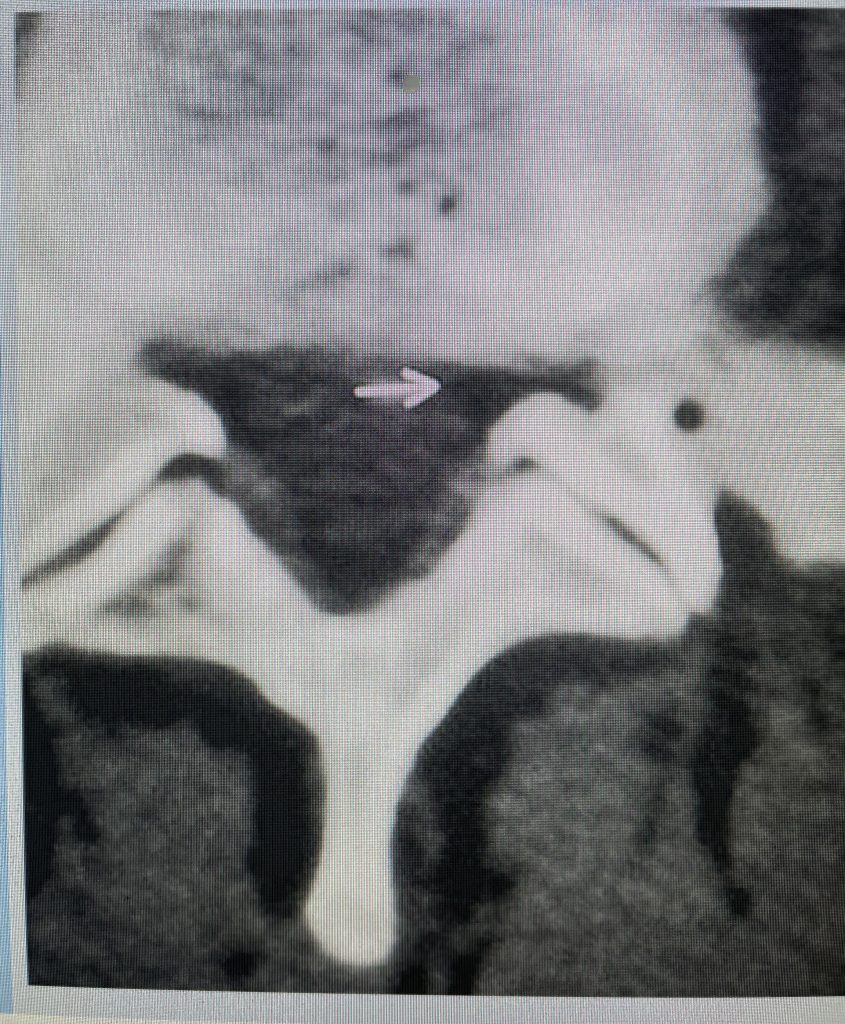

Figure 3: Axial lumbar CT image demonstrating severely narrowed left lateral recess by a significantly hypertrophied facet joint (arrow) The lateral recess is formed by a triangle of the superior facet process, the pedicle, and the anterior margin of the vertebral body. Note the prominence and anterior protrusion of the superior facet process which is more anterior and medially oriented than the inferior process that comprises the facet joint.